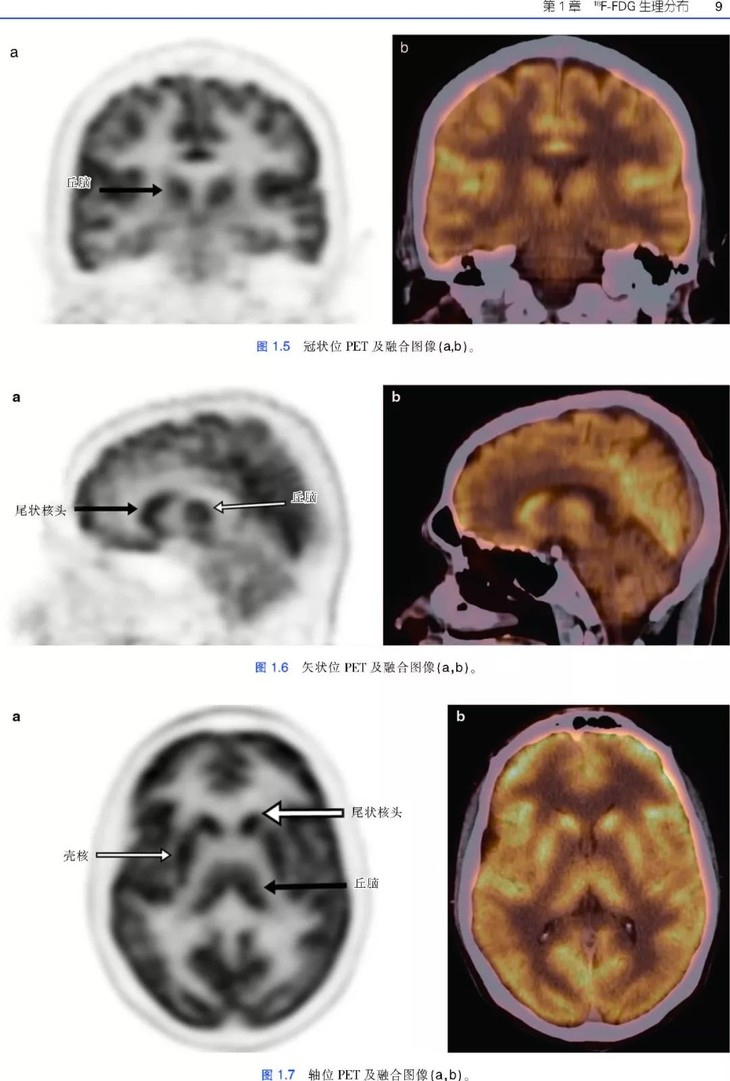

《肿瘤PET/CT成像图谱:病例解析》PET/CT扫描仪的出现,意味着功能代谢信息和解剖数据的融合,开创了医学领域的新纪元,特别是肿瘤学领域。自从PET/CT出现于研究中心,就成为肿瘤影像学中不可或缺的工具。《肿瘤PET/CT成像图谱:病例解析》涵盖了很多关于恶性肿瘤18F-FDG PET/CT诊断和治疗的临床病例。全书共两部分内容,第1部分为FDG PET/CT基础知识,包括18F-FDG的生理分布、正常变异、良性病变和技术伪影。第2部分涵盖了大量临床肿瘤病例,包括常见和罕见表现。每个病例都按照简要病史、影像表现描述、影像表现解释的顺序进行论述,最后是由相关文献支持的学习要点。本书中的所有病例均经组织病理学证实。本书适合核医学、放射学、肿瘤学、肿瘤放射学和核医学技术专业的住院医师和执业医师阅读。

• 涵盖全身各部位肿瘤的临床病例和大量PET/CT图像;

• 图片清晰,内容描述简明扼要,便于读者阅读和理解;